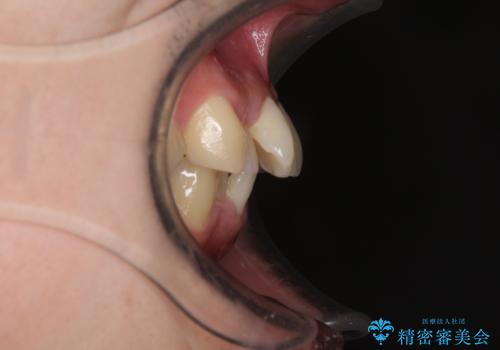

咬合力が非常に強く、抜歯したスペースがなかなか閉じないであろうことは予想できましたが、思っていた以上に期間がかかりました。

前歯のすり減りも著しかったため、仕上げの位置の調整にも期間を要しました。